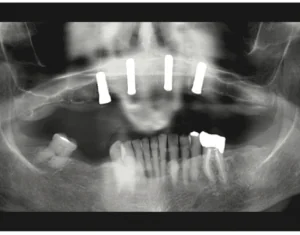

Full-Arch Removable Treatment INTRODUCTION In part 1 of this series, in the March 2023 issue, we discussed single and multi-unit restorations. This is part 2